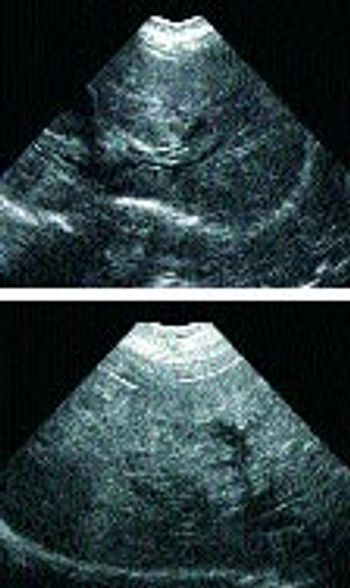

Signalment: Canine, Shepherd cross, 11 years old, female spayed, 46.8 lbs.